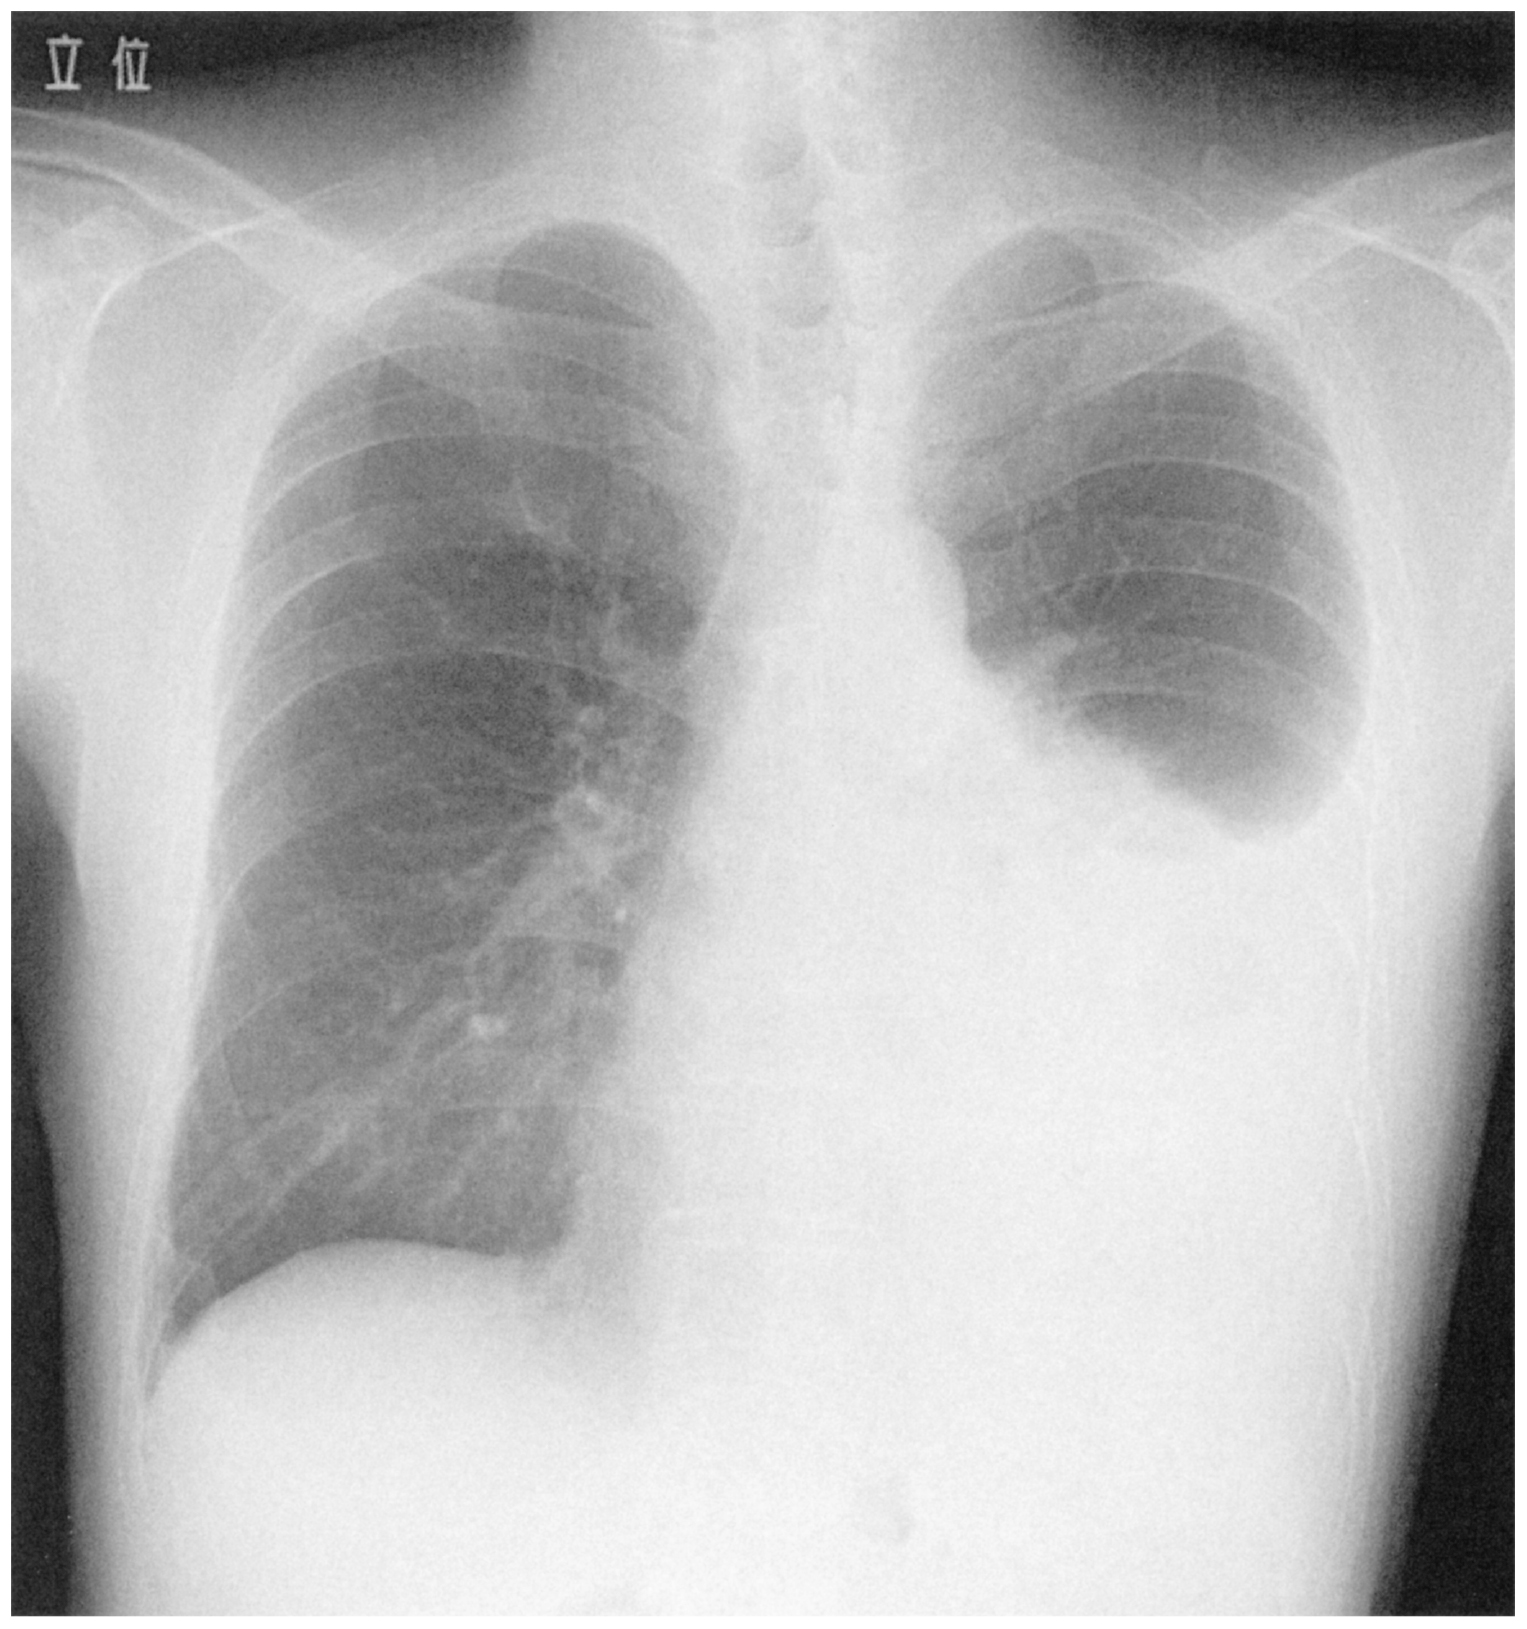

73歳の男性。胸痛,発熱および呼吸困難を主訴に来院した。3日前から咳,倦怠感,胸痛および発熱が出現した。今朝から胸痛が悪化し,呼吸困難も出現したため受診した。痛みは左側胸部から背部に自覚し,咳や深呼吸で増悪する。意識は清明。体温38.5℃。脈拍108/分,整。血圧132/68mmHg。呼吸数24/分。SpO2 92%(room air)。心音に異常を認めない。左下肺野の聴診で呼吸音は減弱し,打診で濁音を認める。腹部は平坦,軟で,肝・脾を触知しない。下肢に浮腫は認めない。心電図に異常を認めない。胸部エックス線写真を下に示す。

無料会員登録していただくと、実際の解説をすべて見ることができます。急性の呼吸困難を主訴とする疾患としては,喉頭浮腫,気道異物,自然気胸,気管支喘息,慢性閉塞性肺疾患の急性増悪などの呼吸器疾患,心不全(急性,慢性の急性増悪),肺血栓塞栓症などの循環器疾患が代表的である。この症例では呼吸器感染症と心不全が疑われるが,胸部エックス線写真は肺炎像というよりも両心不全を示唆する所見を示している。診断:心不全(両心不全)(Nohria分類wet and warm) 選択肢考察 ×a 強い呼吸困難,胸痛などにより安静が保てない場合には,血管拡張による前負荷軽減と,交感神経抑制による心筋酸素消費量の減少を目的としてモルヒネを使用する。この症例ではモルヒネが必要となるほどの興奮状態ではない。